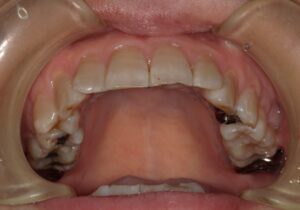

歯冠長延長術

歯ぐきを切除すると共に歯を支える歯槽骨を削って、歯茎を大きく下げるイメージです。歯を長く見せる術式になります。歯肉と骨の両方を削合するので、効果を得やすいですが比較的大きな侵襲がかかります。歯が長く、歯を支える骨が十分にある歯が適応です。ただし今まで口腔内に出ていなかった歯根が口腔内に露出することになるので、知覚過敏のリスクがあります。歯そのものの長さが短いと、歯を支える骨が少なくなり歯が揺れてしまうので、適応症ではありません。

歯肉整形

歯冠長延長術とは少し違い、メスで余分な歯ぐきだけを切除し、歯を長く見せます。ですから比較的低侵襲で行えます。歯を支える骨に問題なく、歯肉だけが多い場合が適応です。こちらも、今まで口腔内に出ていなかった歯根が露出するので知覚過敏のリスクがありますが、歯冠長延長術よりも低リスクです。切除量はさほど大きくできないので、効果は限定的です。